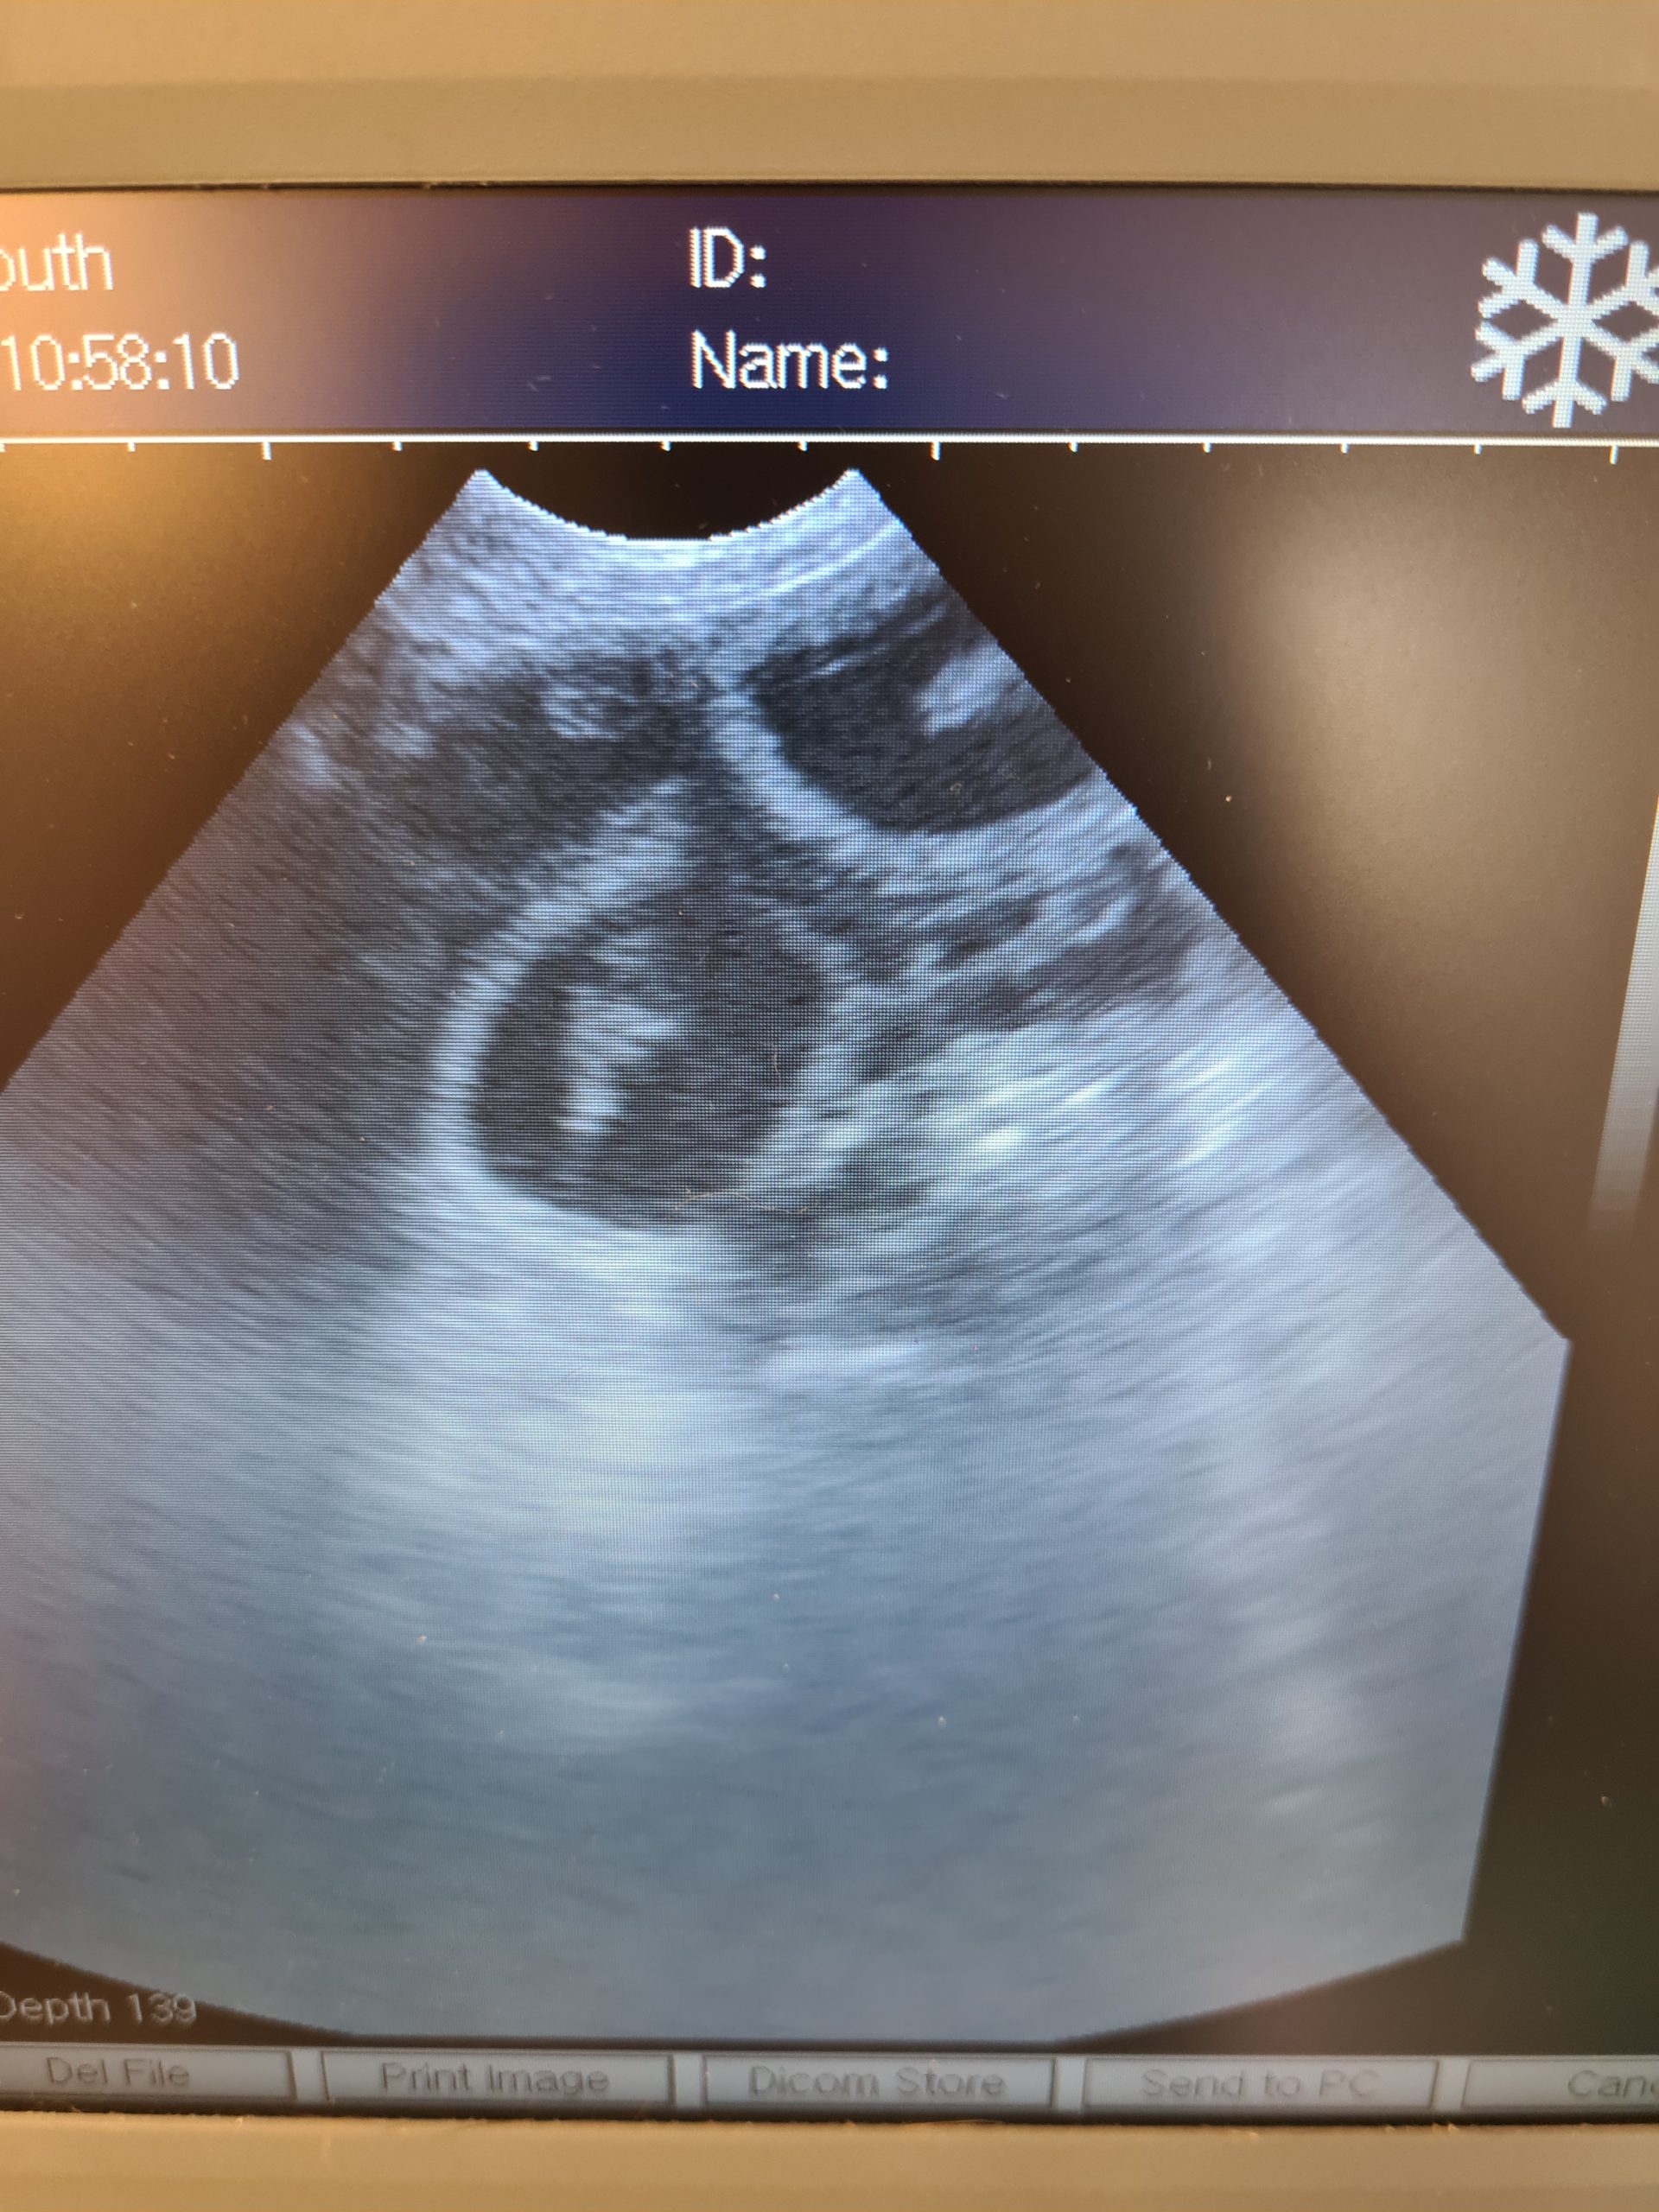

Owner came in adamant her girl wasn’t in pup as she had missed last 2 seasons and no signs ,cytology ai done here she was gobsmacked

owner was convinced bitch weren’t in pup so shocked on scan cytology and a.i. done here